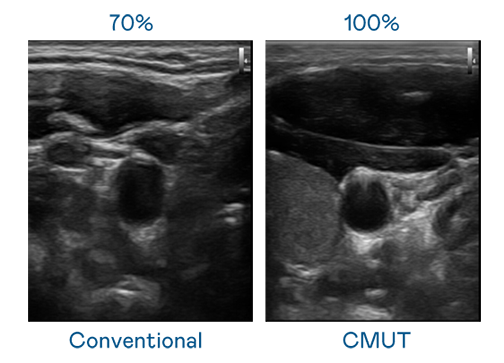

CMUT 技术是一种用电容式微机电元件来产生超音波讯号的技术。与传统 PZT 压电式技术相比,CMUT 频宽增加 30%,更宽频的超音波讯号让影像解析度大幅提升,是实现高影像品质医疗超音波扫描、促进精准医疗发展的关键技术。

超音波影像的解析度高低,首先取决于探头能发出的讯号频宽。u8国际 CMUT 可提供高清晰的超音波讯号,提供高频宽、高灵敏度、影像纹理细节更高的超音波影像,协助医护人员缩短影像判读时间及利用精准的医疗影像进行诊断。